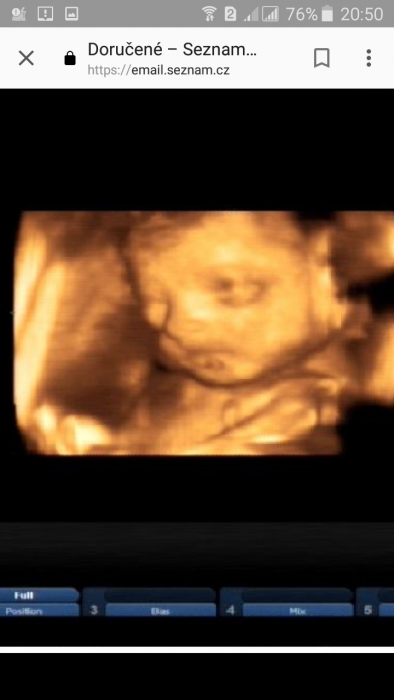

Ahoj holky,koukám ,že se Vám daří vyborne :) I my rosteme krasne :) Zkusím sem nahrát fotku pokojíčku -ještě uspořádat nábytek a nějakou barvicku. ...ale jak nevíme, co to bude,tak musíme počkat :-D A ještě fotku miminka...Můžete tipovat,co to bude :-D

Elena taky bych tipovala holcicku.

El, myslela bych, že je to spíš chlapeček. Trochu mi připomíná ty moje kluky. Ale takhle z obličeje, těžko říct. Jo, kdyby ta fotka byla barevná a byly vidět i nožičky, viděly bychom, jestli má modrý dupačky...